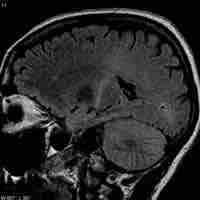

Injuries, Diseases, and Disorders of the Central Nervous System

Thumbnail

Traumatic Brain Injury

Traumatic brain injury (TBI) occurs when an external force injures the brain and can be caused by a direct impact or by acceleration alone.

Cerebrovascular Accident

A cerebrovascular accident results from loss of oxygenated blood to a region of the brain and is typically accompanied by neuronal loss.

Transient Ischemic Attacks

A transient ischemic attack is similar to a stroke; though without permanent damage, it can serve as an important risk factor for stroke.

Alzheimer's Disease

Alzheimer's disease is an age-linked neurodegenerative disorder characterized by marked dementia.

Brain Tumors

A brain tumor is a pathological abnormal growth of cells in the brain.

Amyotrophic Lateral Sclerosis

Amyotrophic lateral sclerosis (ALS) is caused by degeneration of upper and lower motor neurons, resulting in muscle weakness and atrophy.